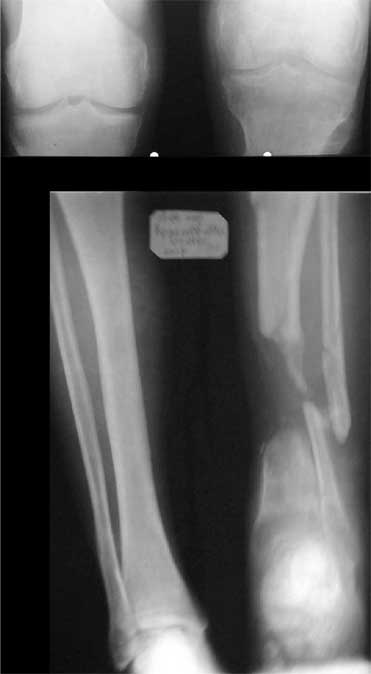

В приложении - моё наблюдение (возможно, уже представлял, тогда

Нога попала в пресс.

Ко мне больной попал черз 1,5-2 года после травмы и нескольких

операций с синегнойной инфекцией на всю голень. Меня пригласили на консультацию

насчет ампутации.

Лечил я его месяцев 8.

Малоберцовка полностью перестроилась, нога опороспособна.

При ходьбе на дальние расстояния пользуется тростью.

Осталась трофическая язва, периодически закрывается.